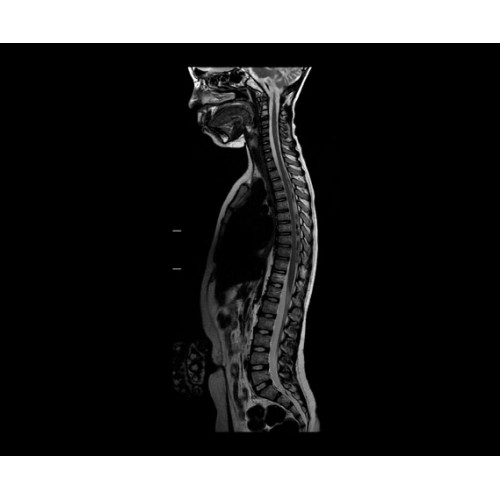

SIGNA PET/MR 3.0T — это гибридная система, в которой совмещаются две принципиально разные технологии — магнитно-резонансную томографию (МРТ) и позитронно-эмиссионную томографию (ПЭТ). Система отличающийся высокой чувствительностью и эффективностью и предназначена для диагностики в области онкологии, неврологии, кардио-васкулярных исследований, исследований воспалительных процессов.

Компания GE Healthcare представляет революционную, полностью интегрированную систему SIGNA PET/MR1, в которой сочетаются времяпролетная технология (TOF) и возможности напряженности магнитного поля 3.0 Тл. Мы поможем вам поднять исследования на более высокий уровень. SIGNA PET/MR позволяет достичь впечатляющей точности и скорости исследований, а благодаря новейшей технологии реконструкции Q.Clear2 качество изображений улучшается в два раза. Кроме того, в систему включен полный набор клинических приложений и гибких катушек для проведения любых видов исследования, открывая для вас возможности визуализации, о которых вы даже не догадывались.

Впечатляющие клинические возможности

Система SIGNA PET/MR предлагает впечатляющие клинические возможности и открывает доступ к наиболее полным пакетам программных приложений.

• МРТ с функцией нулевого времени эхо (ZTE) отличается точностью, возможностью персональных настроек и отсутствием ионизирующего излучения. Она приходит на смену традиционному исследованию на основе рентгеновского излучения. МРТ с функцией нулевого времени эхо (ZTE) на базе SIGNA ПЭТ/МРТ является более надежной и быстрой по сравнению с системами, использующими сверхмалое время эхо (UTE).